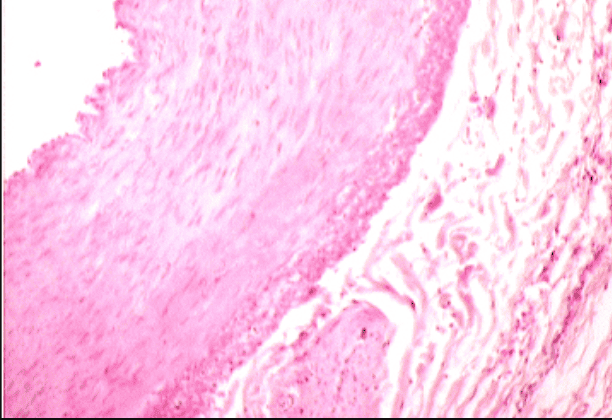

Thyroid Gland

Thyroid Gland